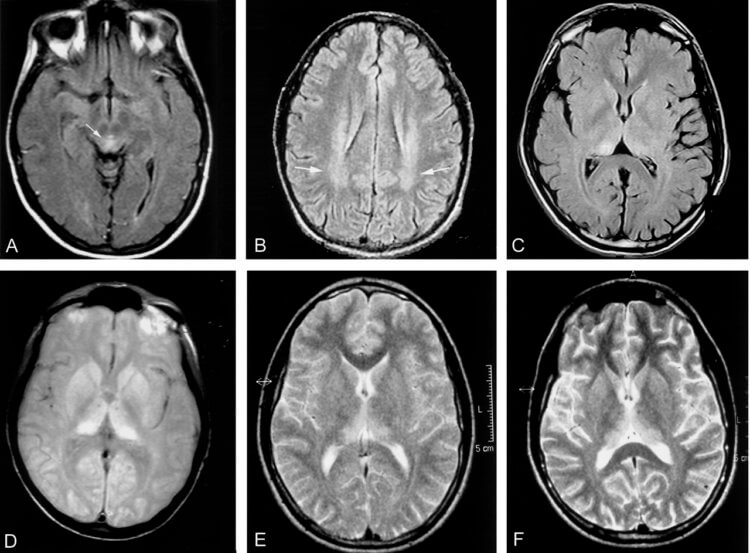

Сканирование мозга пациента с болезнью Крейтцфельдта-Якоба.